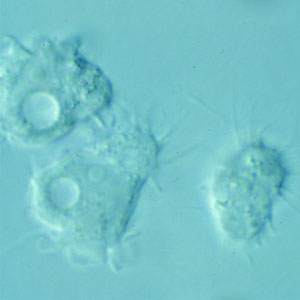

Acanthamoeba trophozoites

spine-like processes